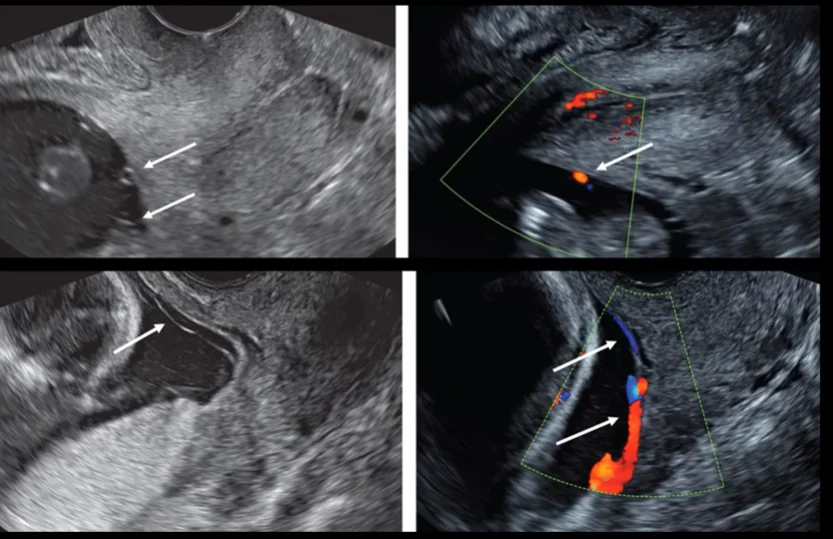

Mạch máu tiền đạo (Vasa Previa )